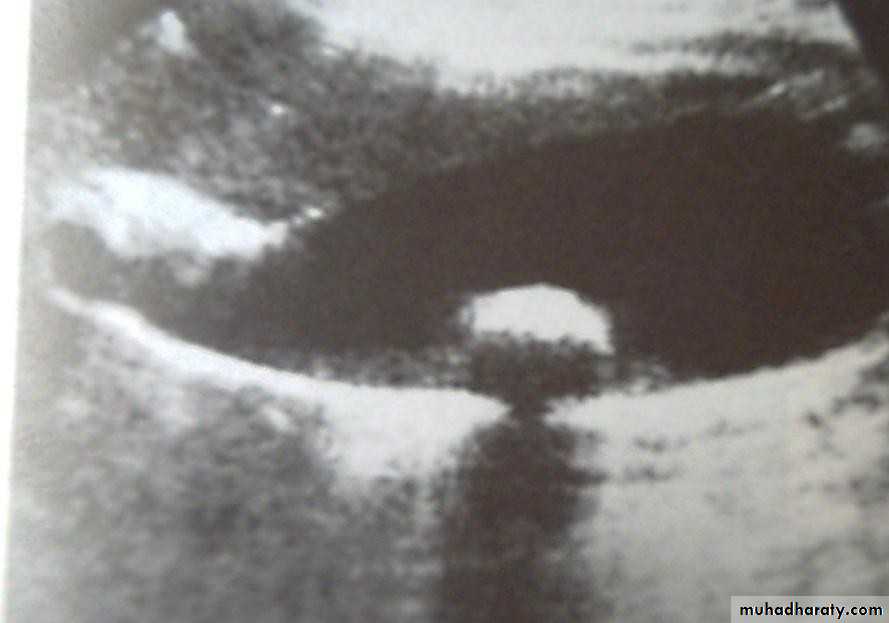

•  Ultrasonography:

•  Non-invasive

•  Standard initial imaging for patient suspected to

• have a gall stone and in jaundiced patients.

•  Ultrasonography:can demonstrate

•  Gall stones

•  GB size, thickness of its wall, presence of inflammation around it, pericystic edema.

•  Size of CBD, occasionally stones in it.

•  Tumour of pancreas.